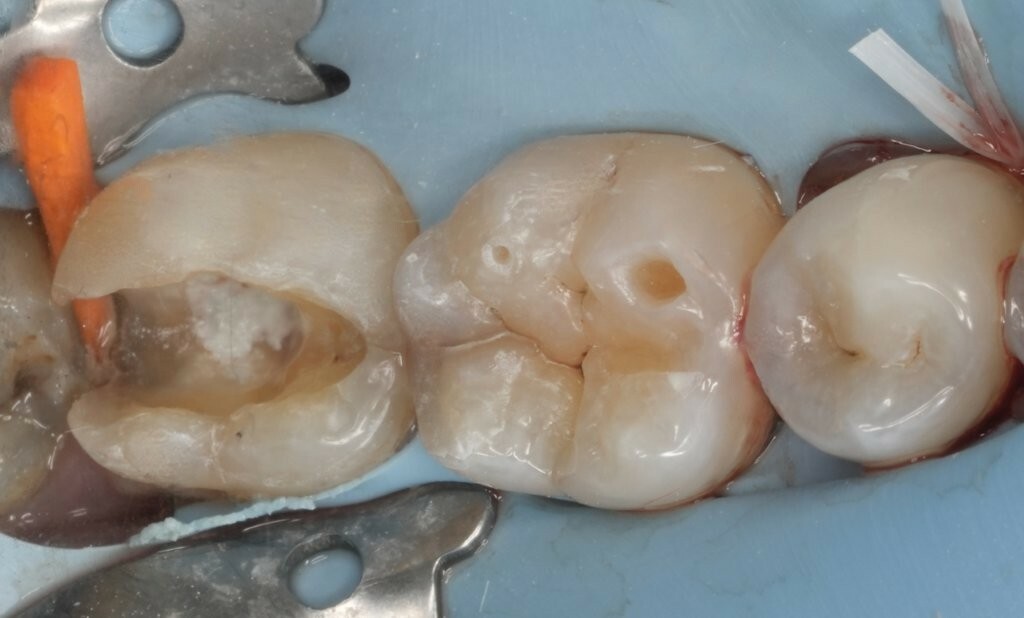

Abbildung 1: Ausgangssituation. Initiale klinische Präsentation einer ausgeprägten, kavitierten, kariösen Läsion an Zahn 37, mit Symptomen einer reversiblen Pulpitis.

Abbildung 3: Direkte Überkappung der eröffneten Pulpa an Zahn 37 mit MTA vpt am zentralen Kavitätenboden.